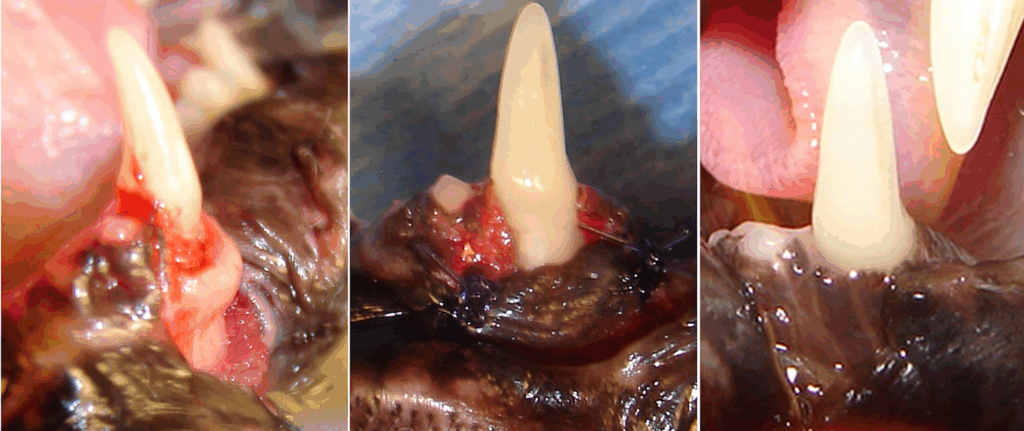

Alveolar osteitis. Notice pronounced bulging appearance of the osseous tissue (bone expansion) at the upper canine tooth.

There was a significant periodontal pocket around this tooth, therefore the canine tooth was extracted.

This mandibular canine tooth had alveolar bone expansion (alveolar osteitis) and bony pocket around the tooth. To save this tooth, a buccal mucoperiosteal flap was raised and the irregular crestal alveolar bone was resected and re-contoured. Flap was apically repositioned and sutured. At three-month recheck alveolar osteitis and periodontal disease were gone and the tooth appeared healthy.